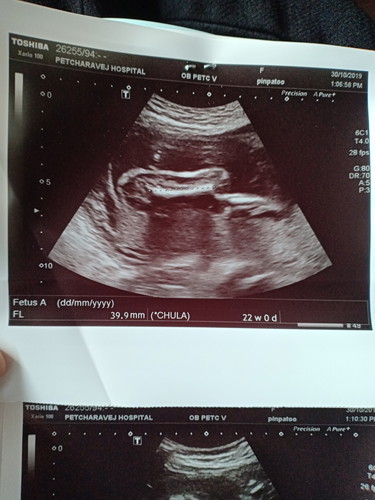

อันนี้คือส่วนไหนคะแม่ๆ

ตอนซาวน์จำได้ แต่กลับมาดูภาพดูไม่ออกค่ะ

น่าจะกระดูกต้นขา